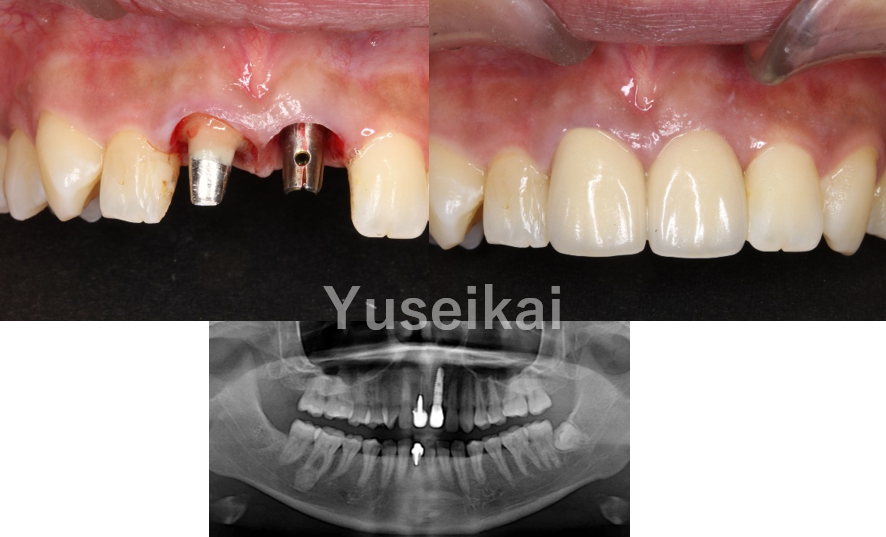

抜歯即時埋入

抜歯即時埋入とは、抜歯と同時にインプラントを埋入する方法です。従来のインプラント治療では、抜歯後に骨の回復を待つ必要があるため治療期間が長くなりますが、抜歯即時埋入では治療にかかる期間を大幅に削減することができます。これにより、患者様の身体的負担が軽減され、早期から通常の機能回復が期待できます。